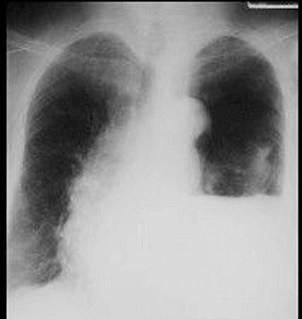

下列哪张图片是脓胸X线表现 ( )A、B、C、D、

问题 下列哪张图片是脓胸X线表现 ( )

选项 A、 B、 C、 D、

答案 B